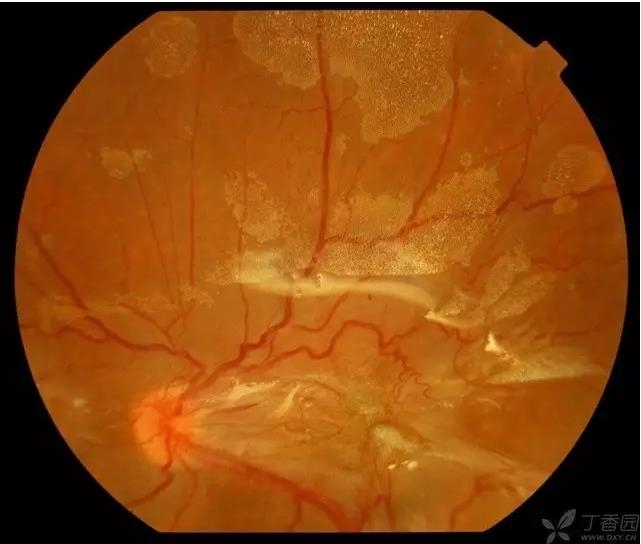

▼硅油乳化后的眼底